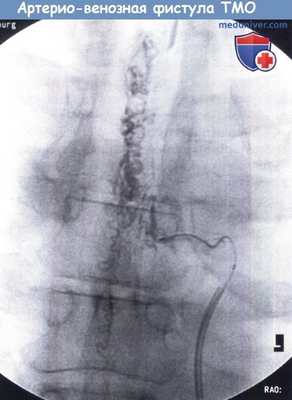

Ангиография: артерио-венозная фистулы ТМО с менингеальными питающими сосудами,

сбрасывающими кровь в расширенные корешковые вены.